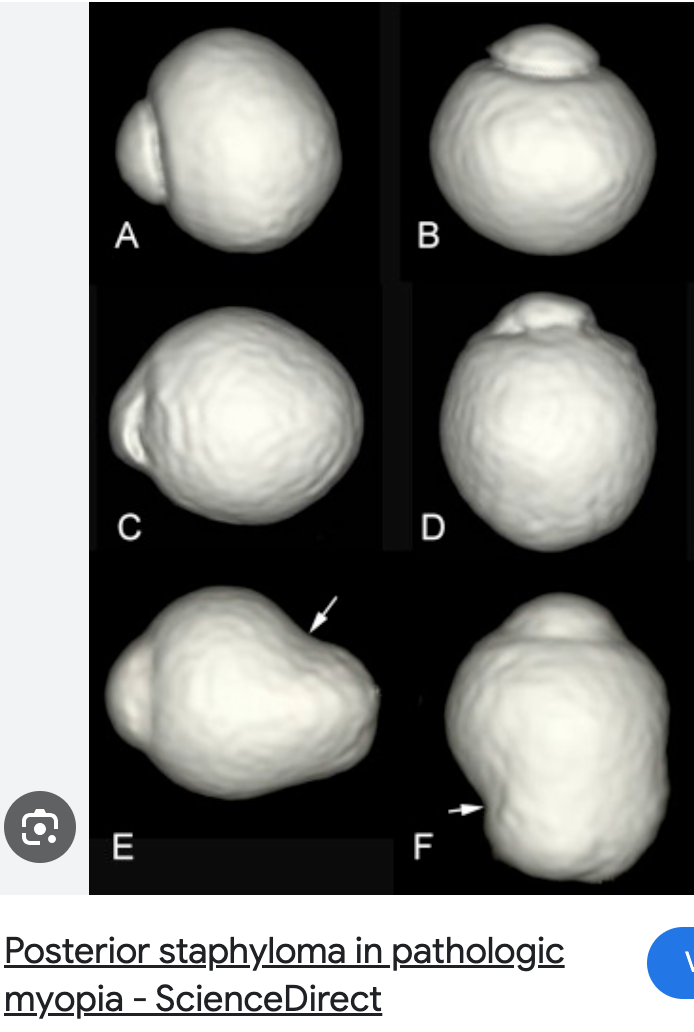

Pathological Myopia/Myopic Degeneration?

High grade + progressive myopia

Hereditary component

Eyeball will not stop elongating

Pts > -6.00D myopia or > 26mm axial length

***NOTE: NOT every high myopia patient has pathological myopia

JUST ones where myopia CONTINUES to progress + present certain signs

Posterior staphyloma (outpouching of post seg as white circles = visible choroid)